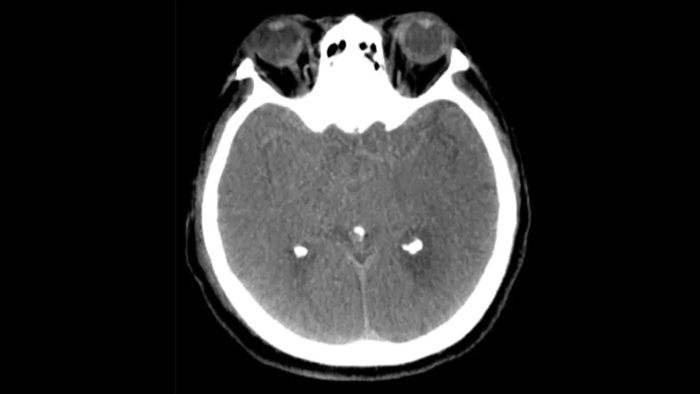

SmartCT Sofy Tissue撮影にて、出血の有無等、治療後の確認を行います。